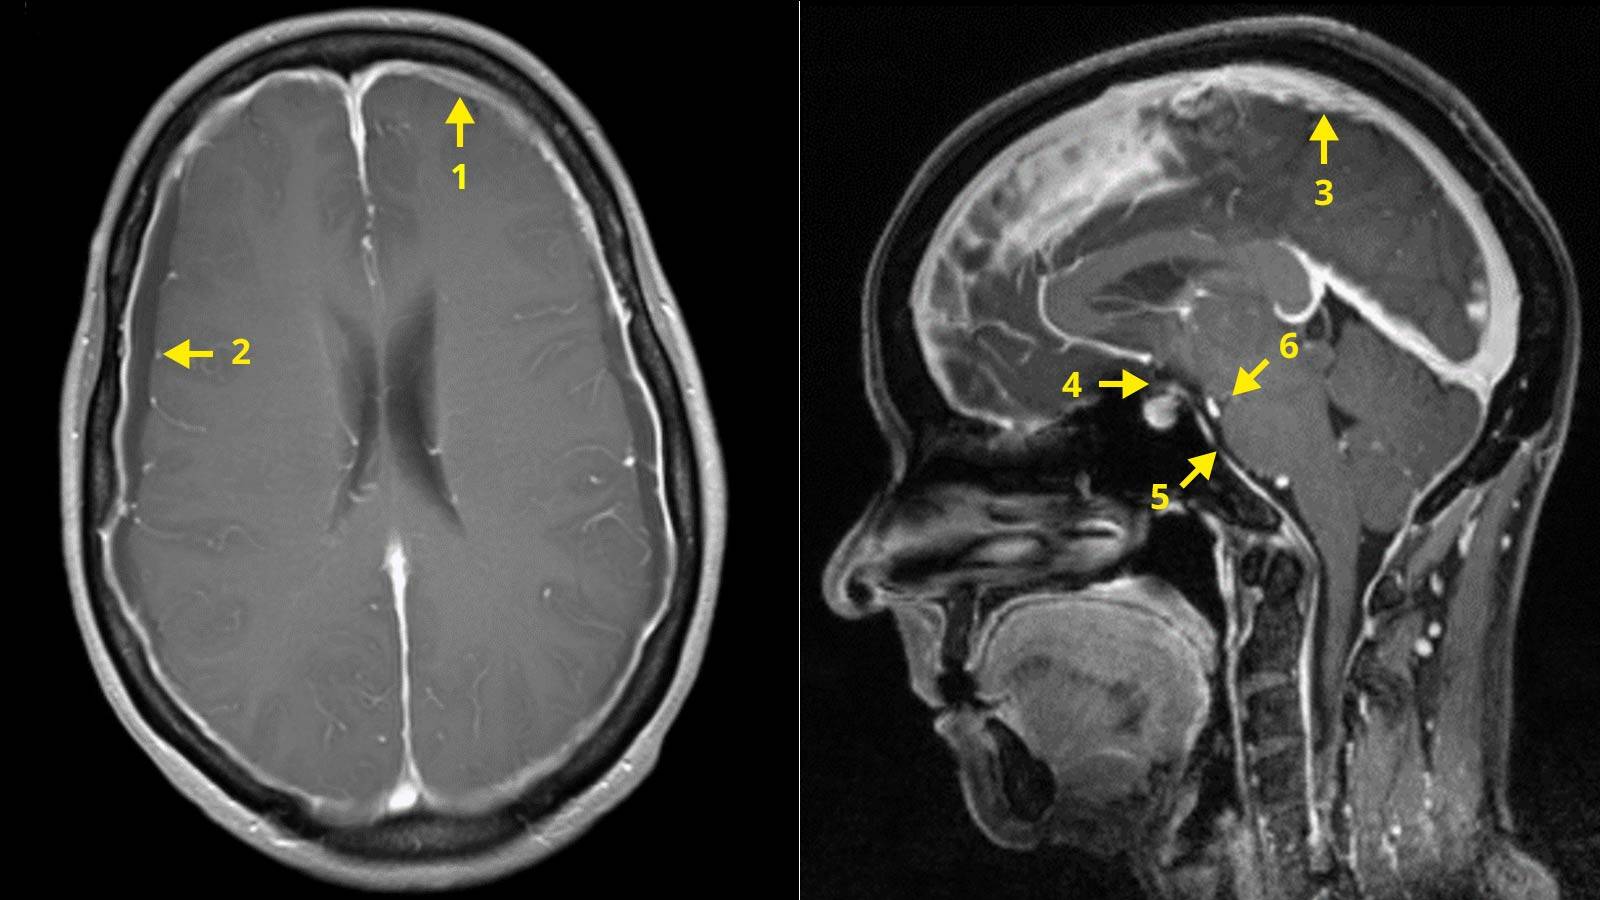

Liquorverlustsyndrom-Beurteilungsschema